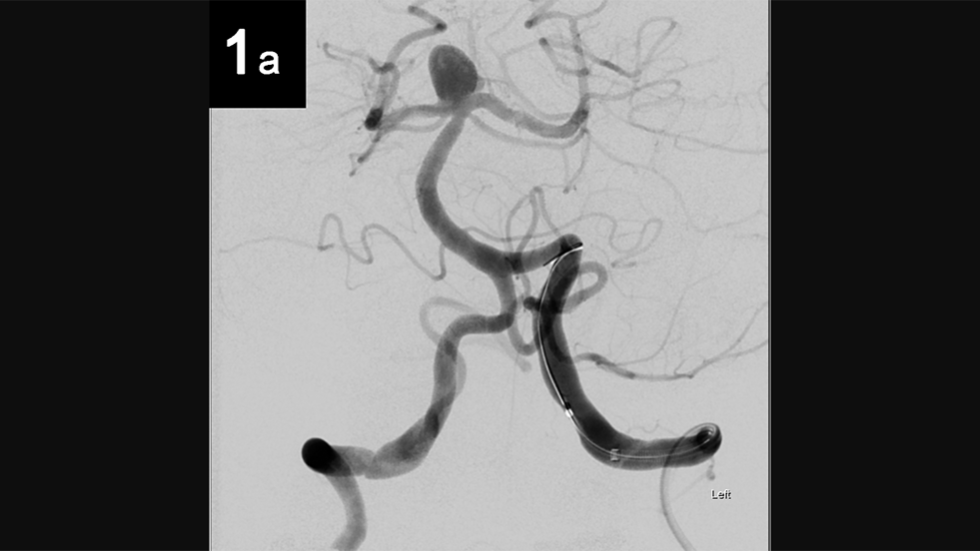

Intrasaccular: 1a

Intrasaccular

Intrasaccular: 2a

2 of 6

Intrasaccular: 1b

4 of 6

Intrasaccular: 2b

5 of 6

Intrasaccular: 3b

6 of 6